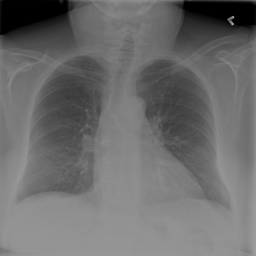

Figure 2: Examples of normal vs. abnormal images of considered datasets. Natural images: (first row) cars vs other classes of CIFAR10 dataset [1], (second row) digits “0” vs digits “1” – “9” of SVHN dataset [2]. Medical images: (third row) healthy tissue vs. tissue with metastases in H&E-stained lymph nodes images from Camelyon16 challenge [3], (fourth row) normal chest X-rays vs. chest X-rays with abnormal findings from NIH dataset [4].

Figure 6: Examples of normal (left) and anomaly (right) images of H&E-stained lymph node of Camelyon16 challenge [3] (top) and chest X-rays of NIH dataset [4] (bottom). We also showed the predicted anomaly score by the proposed method. The higher the score, the more likely to be an anomaly. Notice how the proposed method spots even the borderline cases.